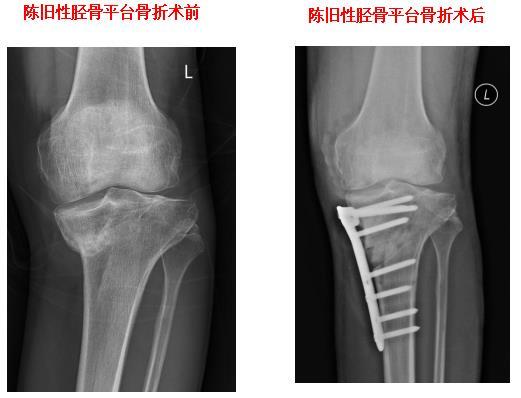

HTO截骨矫正膝关节内翻畸形

胫骨平台粉碎性骨折